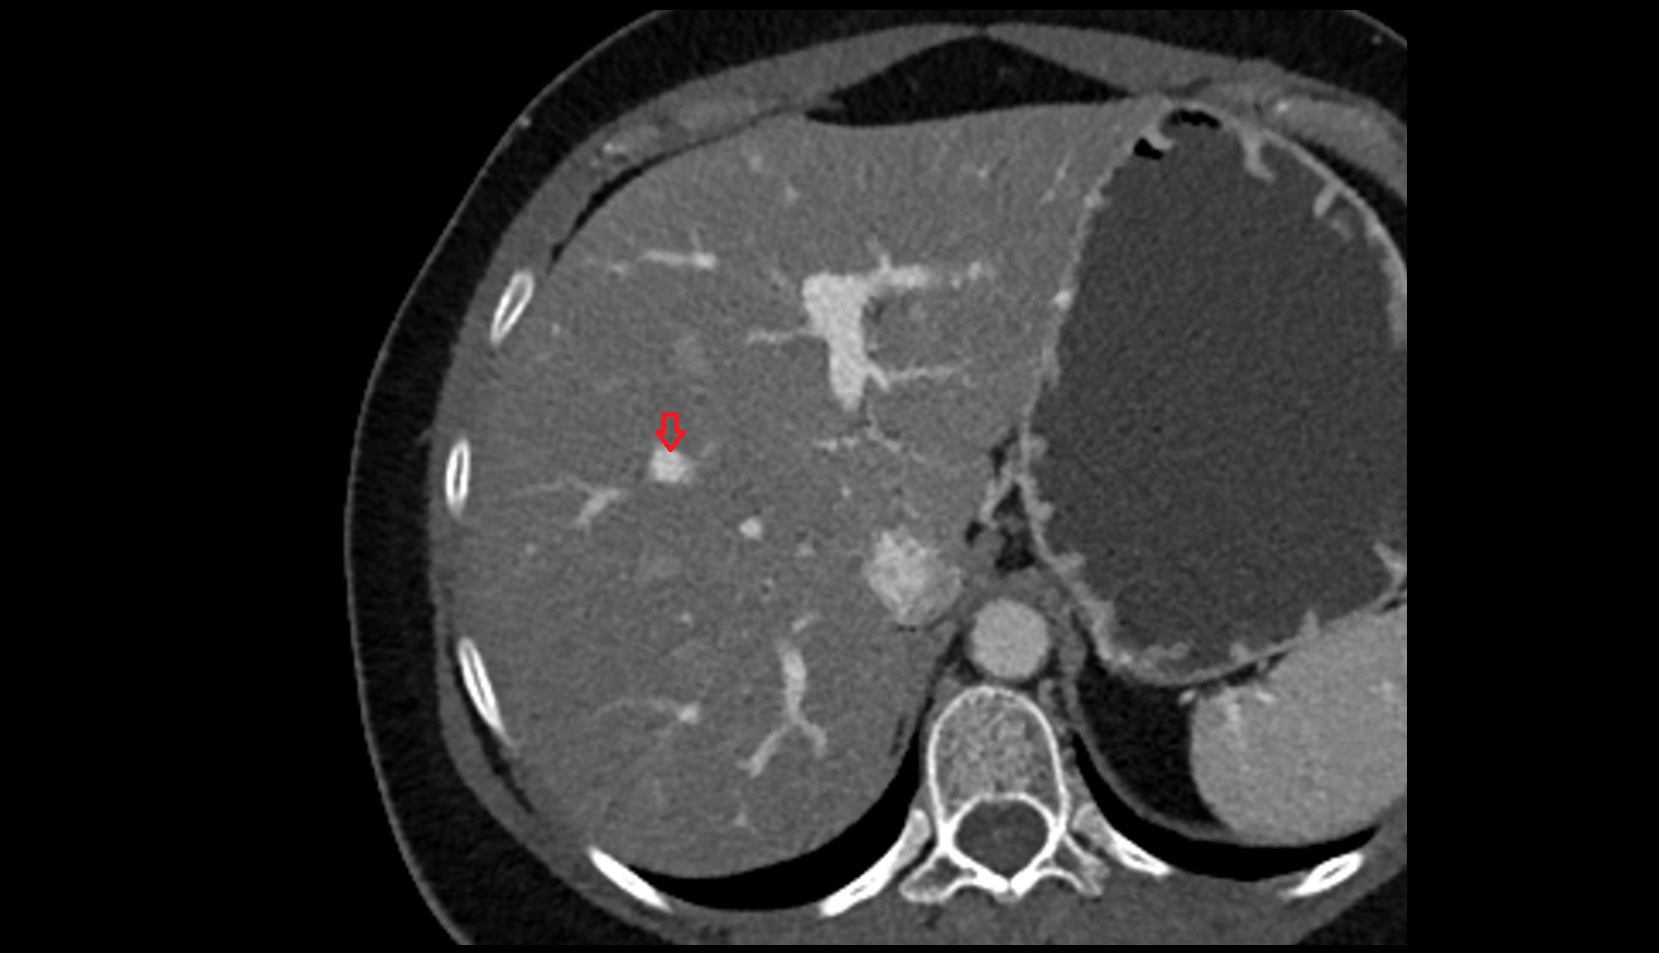

- Right lobe of liver

- Liver

- Left branch of hepatic portal vein

- Right branch of hepatic portal vein

- Portal vein branch to liver segment I

- Portal vein branch to liver segment II

- Portal vein branch to liver segment III

- Portal vein branch to liver segment IV

- Portal vein branch to liver segment V

- Portal vein branch to liver segment VI

- Portal vein branch to liver segment VII

- Portal vein branch to liver segment VIII

- Liver Segment V – Right anteroinferior segment

- Liver Segment VI – Right posteroinferior segment

- Liver Segment VII – Right posterosuperior segment

- Liver Segment VIII – Right anterosuperior segment